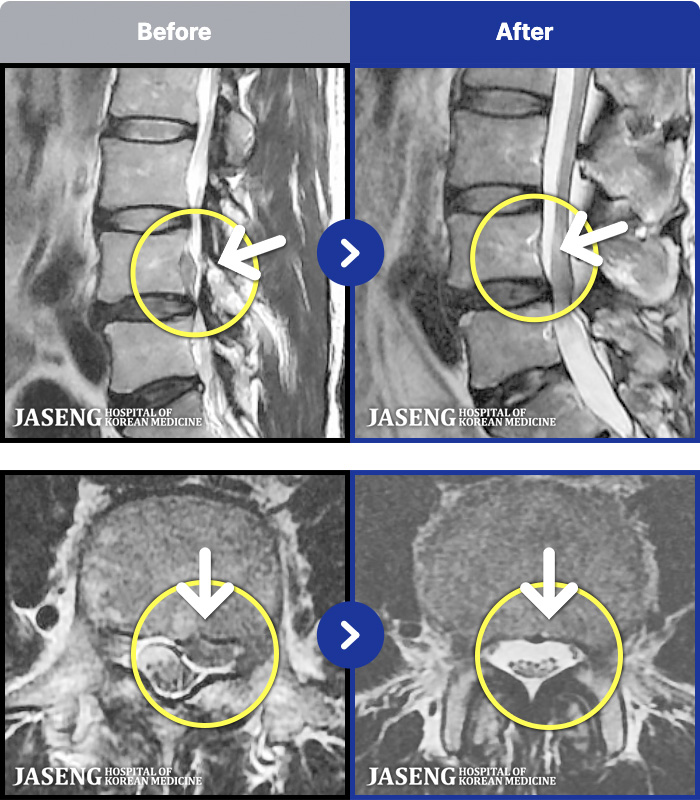

1,291 MRI ũ ʸ Ȯϼ.